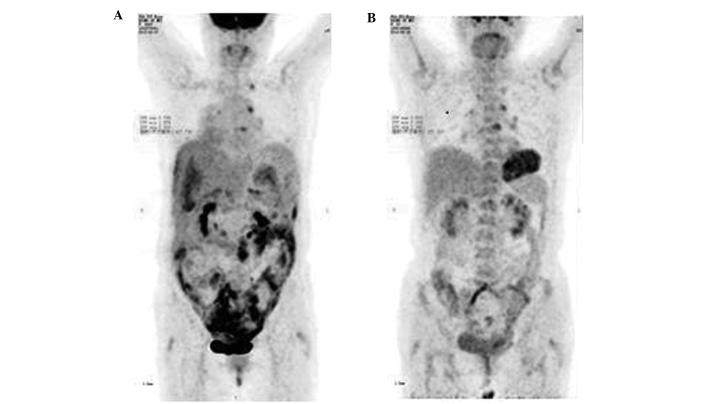

The current study presents the case of a 68-year-old female patient who received biological intensity-modulated radiotherapy (BIMRT) and neoadjuvant chemotherapy for multiple peritoneal metastases of ovarian cancer. The International Federation of Gynecology and Obstetrics disease stage was IIIc. In addition, the patient presented with urination and defecation difficulties. The result of tumor marker detection showed a carcinoembryonic antigen level of 348.2ng/ml, a cancer antigen 125 level of 2,091 U/ml and a cancer antigen 19-9 level of 113 U/ml. Computed tomography (CT) indicated and ovarian cystic or solid package, enlargement of multiple abdominal and retroperitoneal lymph nodes and abdominal cavity effusion. Positron emission tomography/CT indicated multiple internal organ metastases. The center of the ovarian cystic or solid package was considered to be a malignant tumor. A large amount of ascites were detected, as well as abdominal and retroperitoneal lymph node metastasis. The patient was treated with BIMRT at a total dose of 48 Gy, administered as a single 4.0-Gy dose 12 times. In addition, 100 mg cisplatin was administered as a peritoneal perfusion, followed by two cycles of 180 mg Taxol and 100 mg cisplatin. Furthermore, the enlargement of the lymph nodes was reduced and the tumor in the region of the ovary had decreased in size by 90%. The ascites had disappeared and the abdominal pain was greatly improved. At the time of writing this manuscript, the patient was well and without relapse. Therefore, modern radiotherapy techniques, such as BIMRT, may be considered as a beneficial treatment option for ovarian cancer patients with multiple peritoneal metastases in whom surgery is not suitable.

本研究报告了一例68岁女性患者,该患者因卵巢癌多发腹膜转移接受了生物调强放疗(BIMRT)和新辅助化疗。国际妇产科联盟疾病分期为IIIc期。此外,患者还出现了排尿和排便困难。肿瘤标志物检测结果显示,癌胚抗原水平为348.2ng/ml,癌抗原125水平为2091U/ml,癌抗原19-9水平为113U/ml。计算机断层扫描(CT)显示卵巢有囊实性包块,多个腹部和腹膜后淋巴结肿大以及腹腔积液。正电子发射断层扫描/CT显示多处内脏转移。卵巢囊实性包块的中心被认为是恶性肿瘤。检测到大量腹水以及腹部和腹膜后淋巴结转移。患者接受了总剂量为48Gy的BIMRT治疗,每次剂量为4.0Gy,共12次。此外,给予100mg顺铂进行腹腔灌注,随后进行两个周期的180mg紫杉醇和顺铂100mg治疗。此外,淋巴结肿大有所减轻,卵巢区域的肿瘤大小缩小了90%。腹水消失,腹痛明显改善。在撰写本手稿时,患者情况良好,无复发。因此,对于不适合手术的卵巢癌多发腹膜转移患者,现代放疗技术如BIMRT可被视为一种有益的治疗选择。